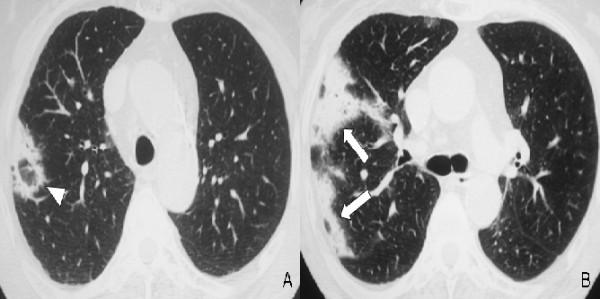

Here, we describe a rare case of acute fibrinous and organising pneumonia, in an otherwise healthy 65-year-old Greek woman who complained of dry cough, fever, weight loss and progressive dyspnoea. She had never been a smoker. Her clinical symptoms showed a rapid deterioration in the two weeks before admission, despite a course of oral antibiotics. After excluding infection and malignancy with routine laboratory tests and flexible bronchoscopy, high resolution computed tomography and video assisted thoracoscopic lung biopsy were performed. Diagnosis was based on radiological features typical of community organising pneumonia coupled with pathologic features characteristic of acute fibrinous and organising pneumonia. The patient was treated with corticosteroids and showed excellent clinical and radiological response three months after treatment initiation.

在此,我们描述一例罕见的急性纤维蛋白性和机化性肺炎病例,患者为一名65岁健康的希腊女性,主诉干咳、发热、体重减轻和进行性呼吸困难。她从不吸烟。尽管接受了口服抗生素治疗,但在入院前两周她的临床症状迅速恶化。通过常规实验室检查和可弯曲支气管镜检查排除感染和恶性肿瘤后,进行了高分辨率计算机断层扫描和电视辅助胸腔镜肺活检。诊断基于社区获得性机化性肺炎的典型放射学特征以及急性纤维蛋白性和机化性肺炎的特征性病理特征。患者接受了皮质类固醇治疗,治疗开始三个月后临床和放射学反应良好。